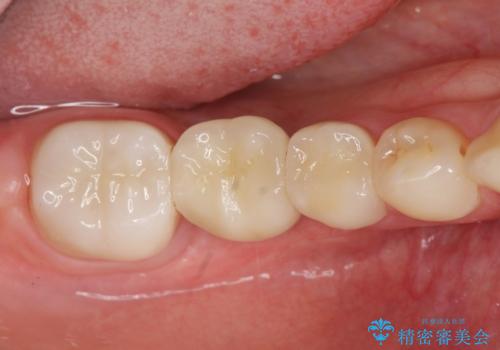

臼歯インプラント補綴

- 70万円(仮歯・ジルコニアクラウン×3 ストローマンインプラント・アバットメント)費用は治療当時の料金となります

歯を失ってからの時間が経過し骨が吸収してしまっていても、造骨を行うことで予知性の高いインプラント治療を行うことができます。